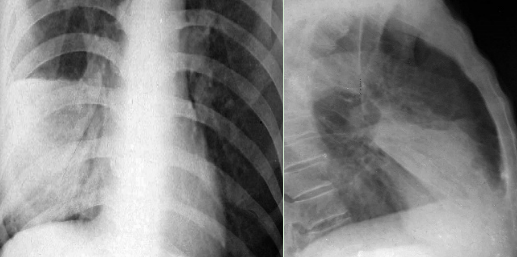

健康中国重庆行动 | 健康中国巴渝行·好医声科普丨养肺护肺 远离肺炎

健康中国重庆行动 | 健康中国巴渝行·好医声科普 | 趁“冷”打劫 警惕肺炎突袭